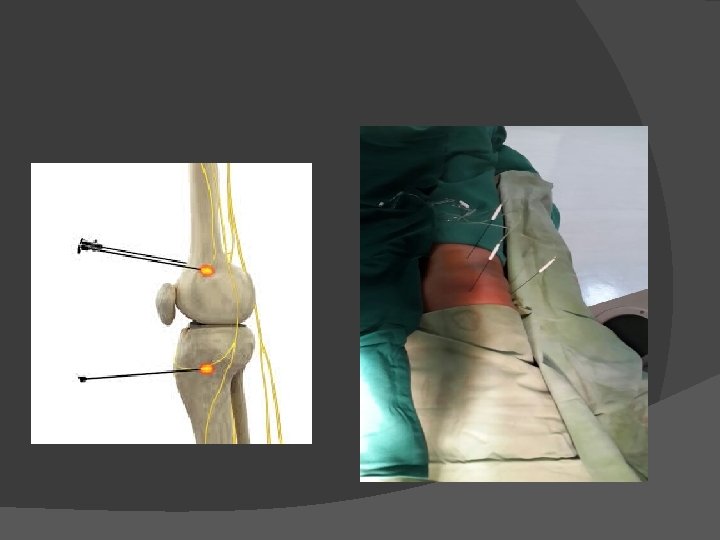

Osteoarthritis Pain � nyeri pada lutut � nyeri bertambah jika beraktifitas � lutut berbunyi � gangguan gerak aktif dan pasif

Genicular neurolysis

� Kasus 5 Wanita, 67 tahun, mengeluh nyeri sendi lutut kanan sejak 2 tahun. Di diagnosis osteoarthritis grade 3 dan dianjurkan untuk operasi Total knee replacement namun menolak. Genicular nerve neurolysis